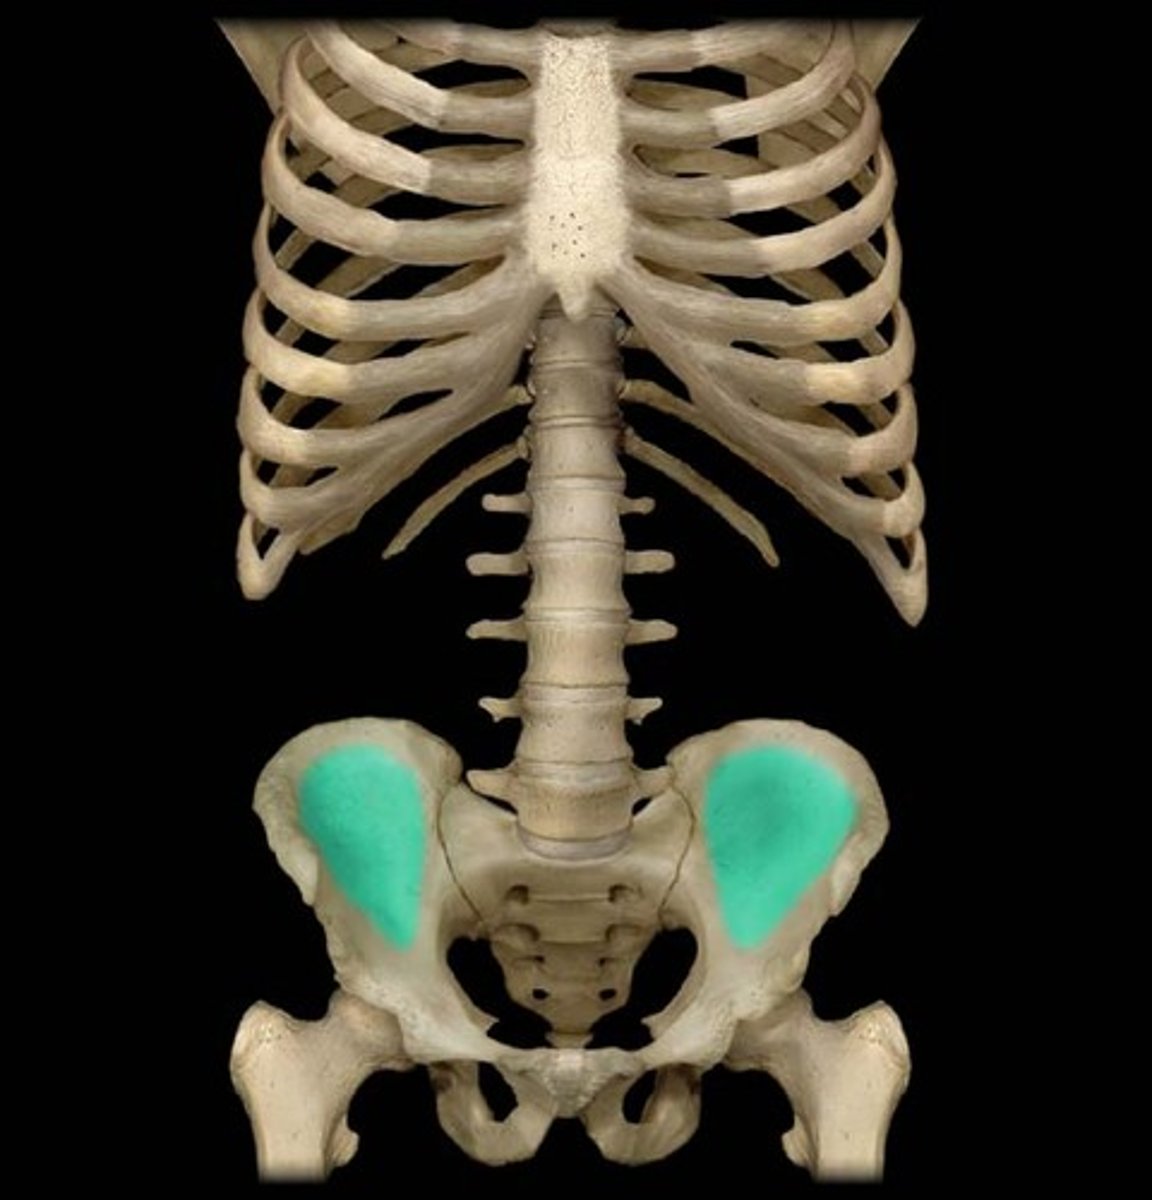

iliac fossa

The broad, slightly concave inner surface of the ilium.